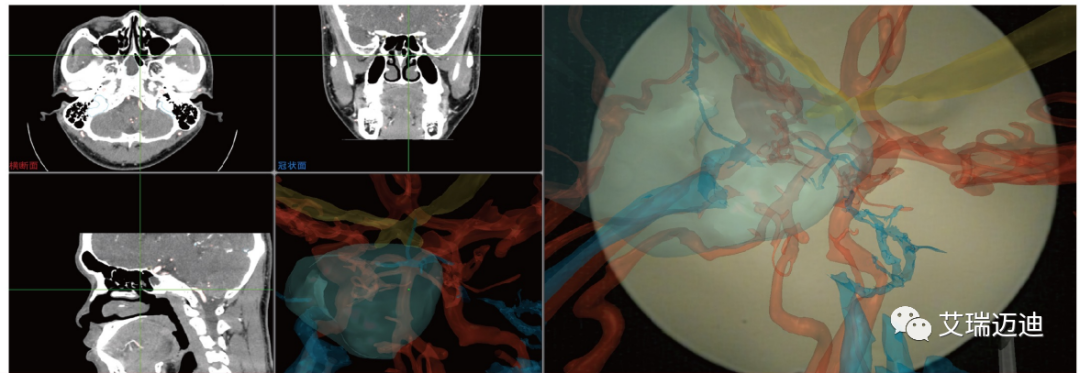

展会上,艾瑞迈迪内窥镜颅底外科手术导航设备成为展会关注焦点。艾瑞迈迪内窥镜颅底外科手术导航设备借助术前CT/MRI图像为医生精准呈现患者头颈部的解剖结构信息,并与术中内镜影像融合进行增强现实可视化,引导医生精准、安全地完成神经外科的颅底肿瘤手术。

第一,内镜融合显示功能。特有的增强现实内镜显示功能,将内镜视野融合术前CT影像,单屏显示所有术中重要的影像内容,消除医生术中多屏浏览的困扰;

内镜融合显示功能